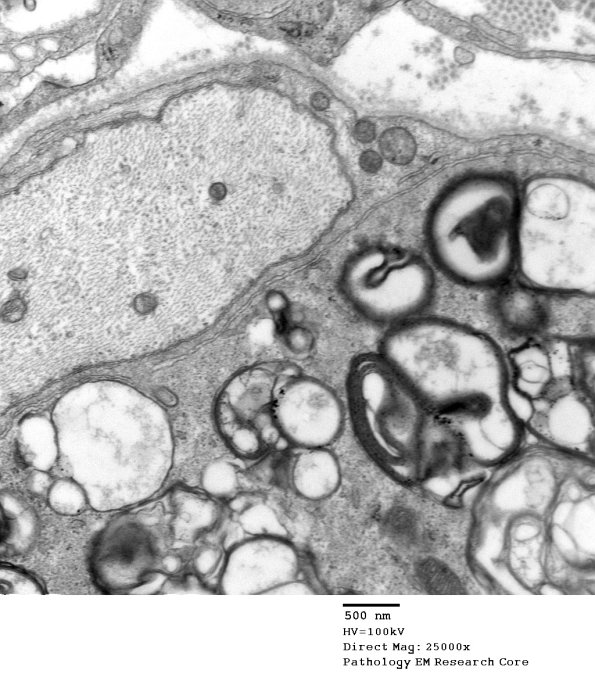

A naked axon surrounded by macrophage processes containing myelin debris. (electron micrographs)